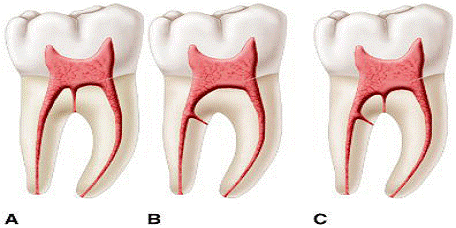

Vertuci, folosind dintii transparentizati la care sistemul endodontic a fost colorat cu hematoxilina, a descoperit un sistem mult mai complex(figura 9). Ei au identificat opt tipuri de sisteme ce pot fi descries dupa cum urmeaza.

Figura 9. Clasificarea lui

Vertucci

Singurul dinte ce a prezentat toate tipurile de sisteme a fost premolarul 2 superior.